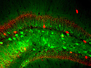

Crossed Bones

Understanding bone tumours by watching them as they grow

Cancers that spread to bones are often difficult to treat, but finding out how tumour and bone cells live side by side may help to heal osteolytic lesions – tears created in bone tissue as a tumour grows inside. Intravital microscopy watches as this lesion, in mouse bone, widens over several days. From blue to green to red – consecutive overlapping pictures show the fringe of the hole eaten away by bone resorption – when bone cells are broken down. This bone tissue was actually grown in a lab under a mouse’s skin, with a thin surface ideal for peering through. Treating the lesion with a chemical called zoledronic acid slows the bone’s deterioration – just as it does in human patients – but doesn’t stop the cancer growing. Using biological models like this, scientists can now test combinations of drugs that preserve the bone, while targeting the cancer cells inside.